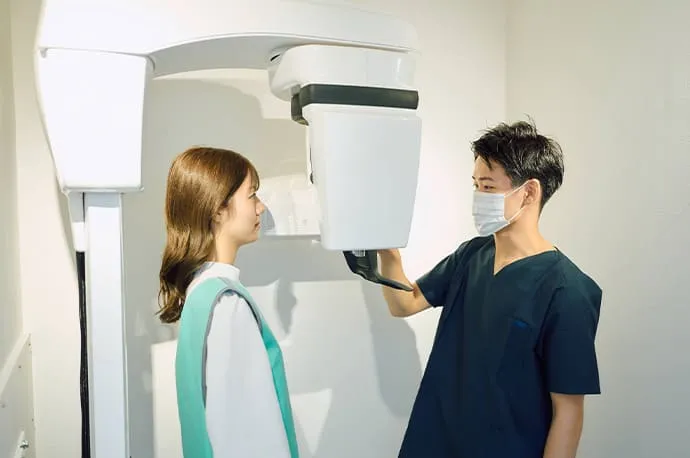

根尖部(根の先)の化膿の診断

歯の根の先が化膿しているかどうかの診断は、歯髄の診断と比べると比較的行いやすく、主にレントゲン検査を用いて確認します。

当院では、すべての患者さまにCT撮影を無料で実施しています。これにより、まだ痛みが出ていない段階の化膿や、通常のレントゲンでは見つけにくい小さな病変まで確認することが可能です。